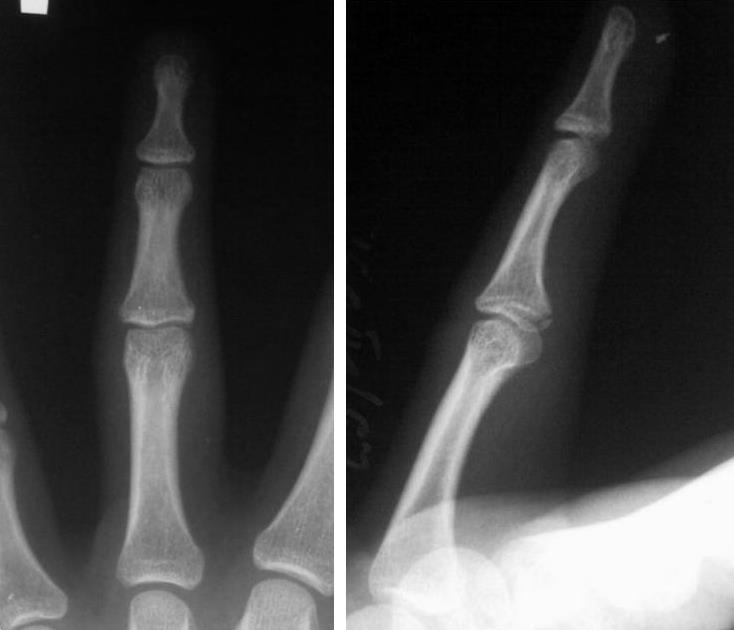

Нет, нет уважаемый Валентин Львович, я имею в виду про среднюю фалангу 3 пальца(краевой перелом), в проксимальном межфаланговом суставе.

Перелом основания средней фаланги III пальца, причем бесспорно. Чётко видена линия перелома. Отёк мягких тканей III пальца.

В данном случае четко определяется линия перелома - указана стрелкой. Для сравнения - на фалангах 4 и 2 пальцев её, разумеется, нет.

Вот нашла три похожих переломчика у подростков.

По поводу детских снимков - не такие они уж и детские, снимки подростков по 16-17 лет, ростковые зоны то уже закрыты.